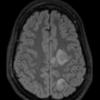

INFECTION

Bacteria

Abscess

Abscess, Early (Cerebritis - Initial Wall Formation)